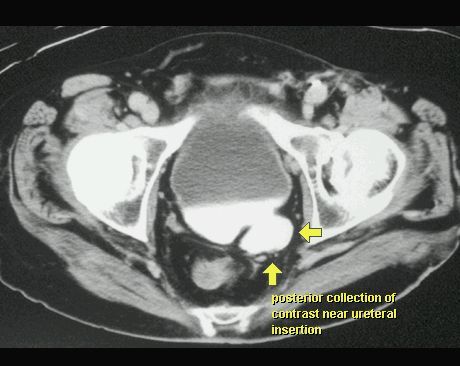

UCHYŁEK PĘCHERZA MOCZOWEGO

TK